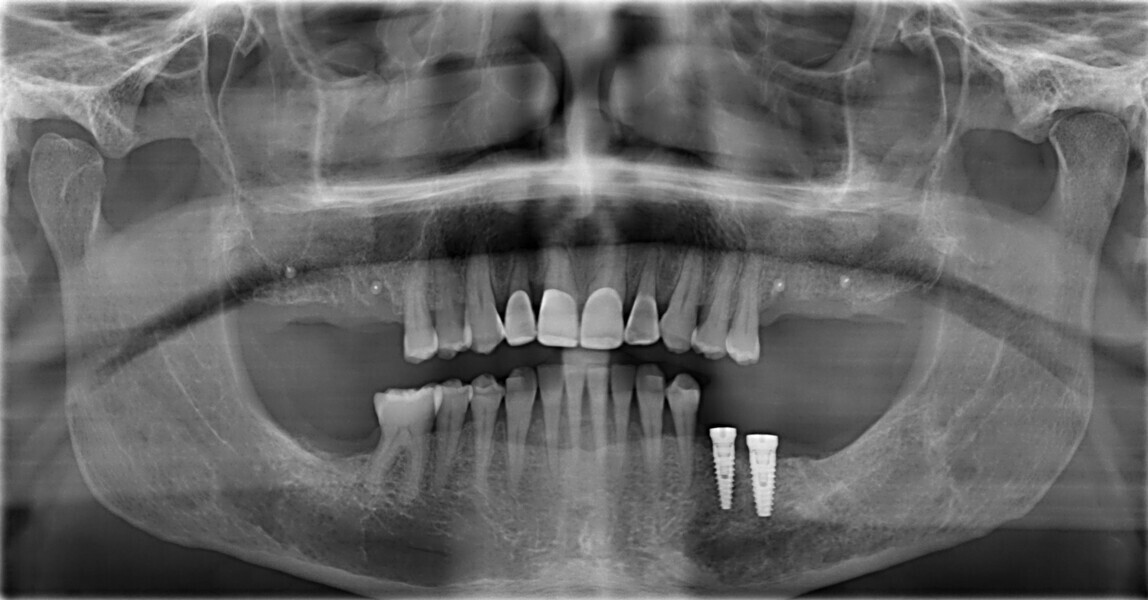

This patient, like all patients requiring interdisciplinary rehabilitation, had to first undergo periodontal treatment and caries restoration (Fig. 17). At the same time, it was important to rehabilitate swallowing with Froggymouth and relax the masticatory muscles and relieve the TMJs with an occlusal device. We could then study the orthodontic treatment plan using Invisalign ClinCheck (Align Technology) and showed the treatment plan to the interdisciplinary team and to the patient (Fig. 18). We were then able to create the correct sequence of orthodontic treatment, bone augmentation and implant surgery needed for the posterior edentulous spaces.

After the first phase of aligner treatment, we had achieved better inter-arch coherence, better maxillary arch expansion, and some space for improving the anterior tooth proportions restoratively (Fig. 19). We then temporarily restored the anterior teeth directly with composite, closing the spaces, improving the tooth proportions and further increasing the maxillary arch expansion (Fig. 20). We used restorative arch expansion to reduce the orthodontic destabilisation of the teeth to achieve the correct inter-arch coherence and retain the teeth in the cortical bone.38 A refinement aligner phase was undertaken to improve the final alignment of the gingival zenith and to improve the inter-arch coherence (Fig. 21). The periods of the first orthodontic phase and of the refinement were used to augment the mandibular and maxillary bone and to place the implants (Fig. 22). At the end of the orthodontic treatment, the case was finalised with ceramic veneers in the anterior area and temporary restorations on the implants in the posterior area (Figs. 23–26).